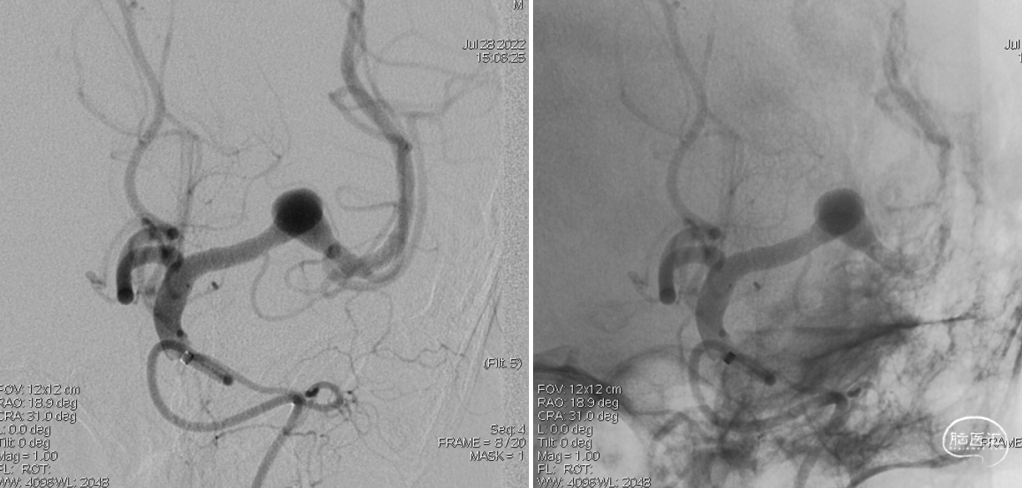

DSA检查:L-M1段夹层动脉瘤(07-28)。

术中2-D造影可见远端血管通畅良好,晚期动脉瘤内造影剂滞留明显。(07-28)

正位

侧位

动脉瘤明显缩小,仅小部分动脉瘤显影,3D可见支架打开充分贴壁良好。

正位

侧位